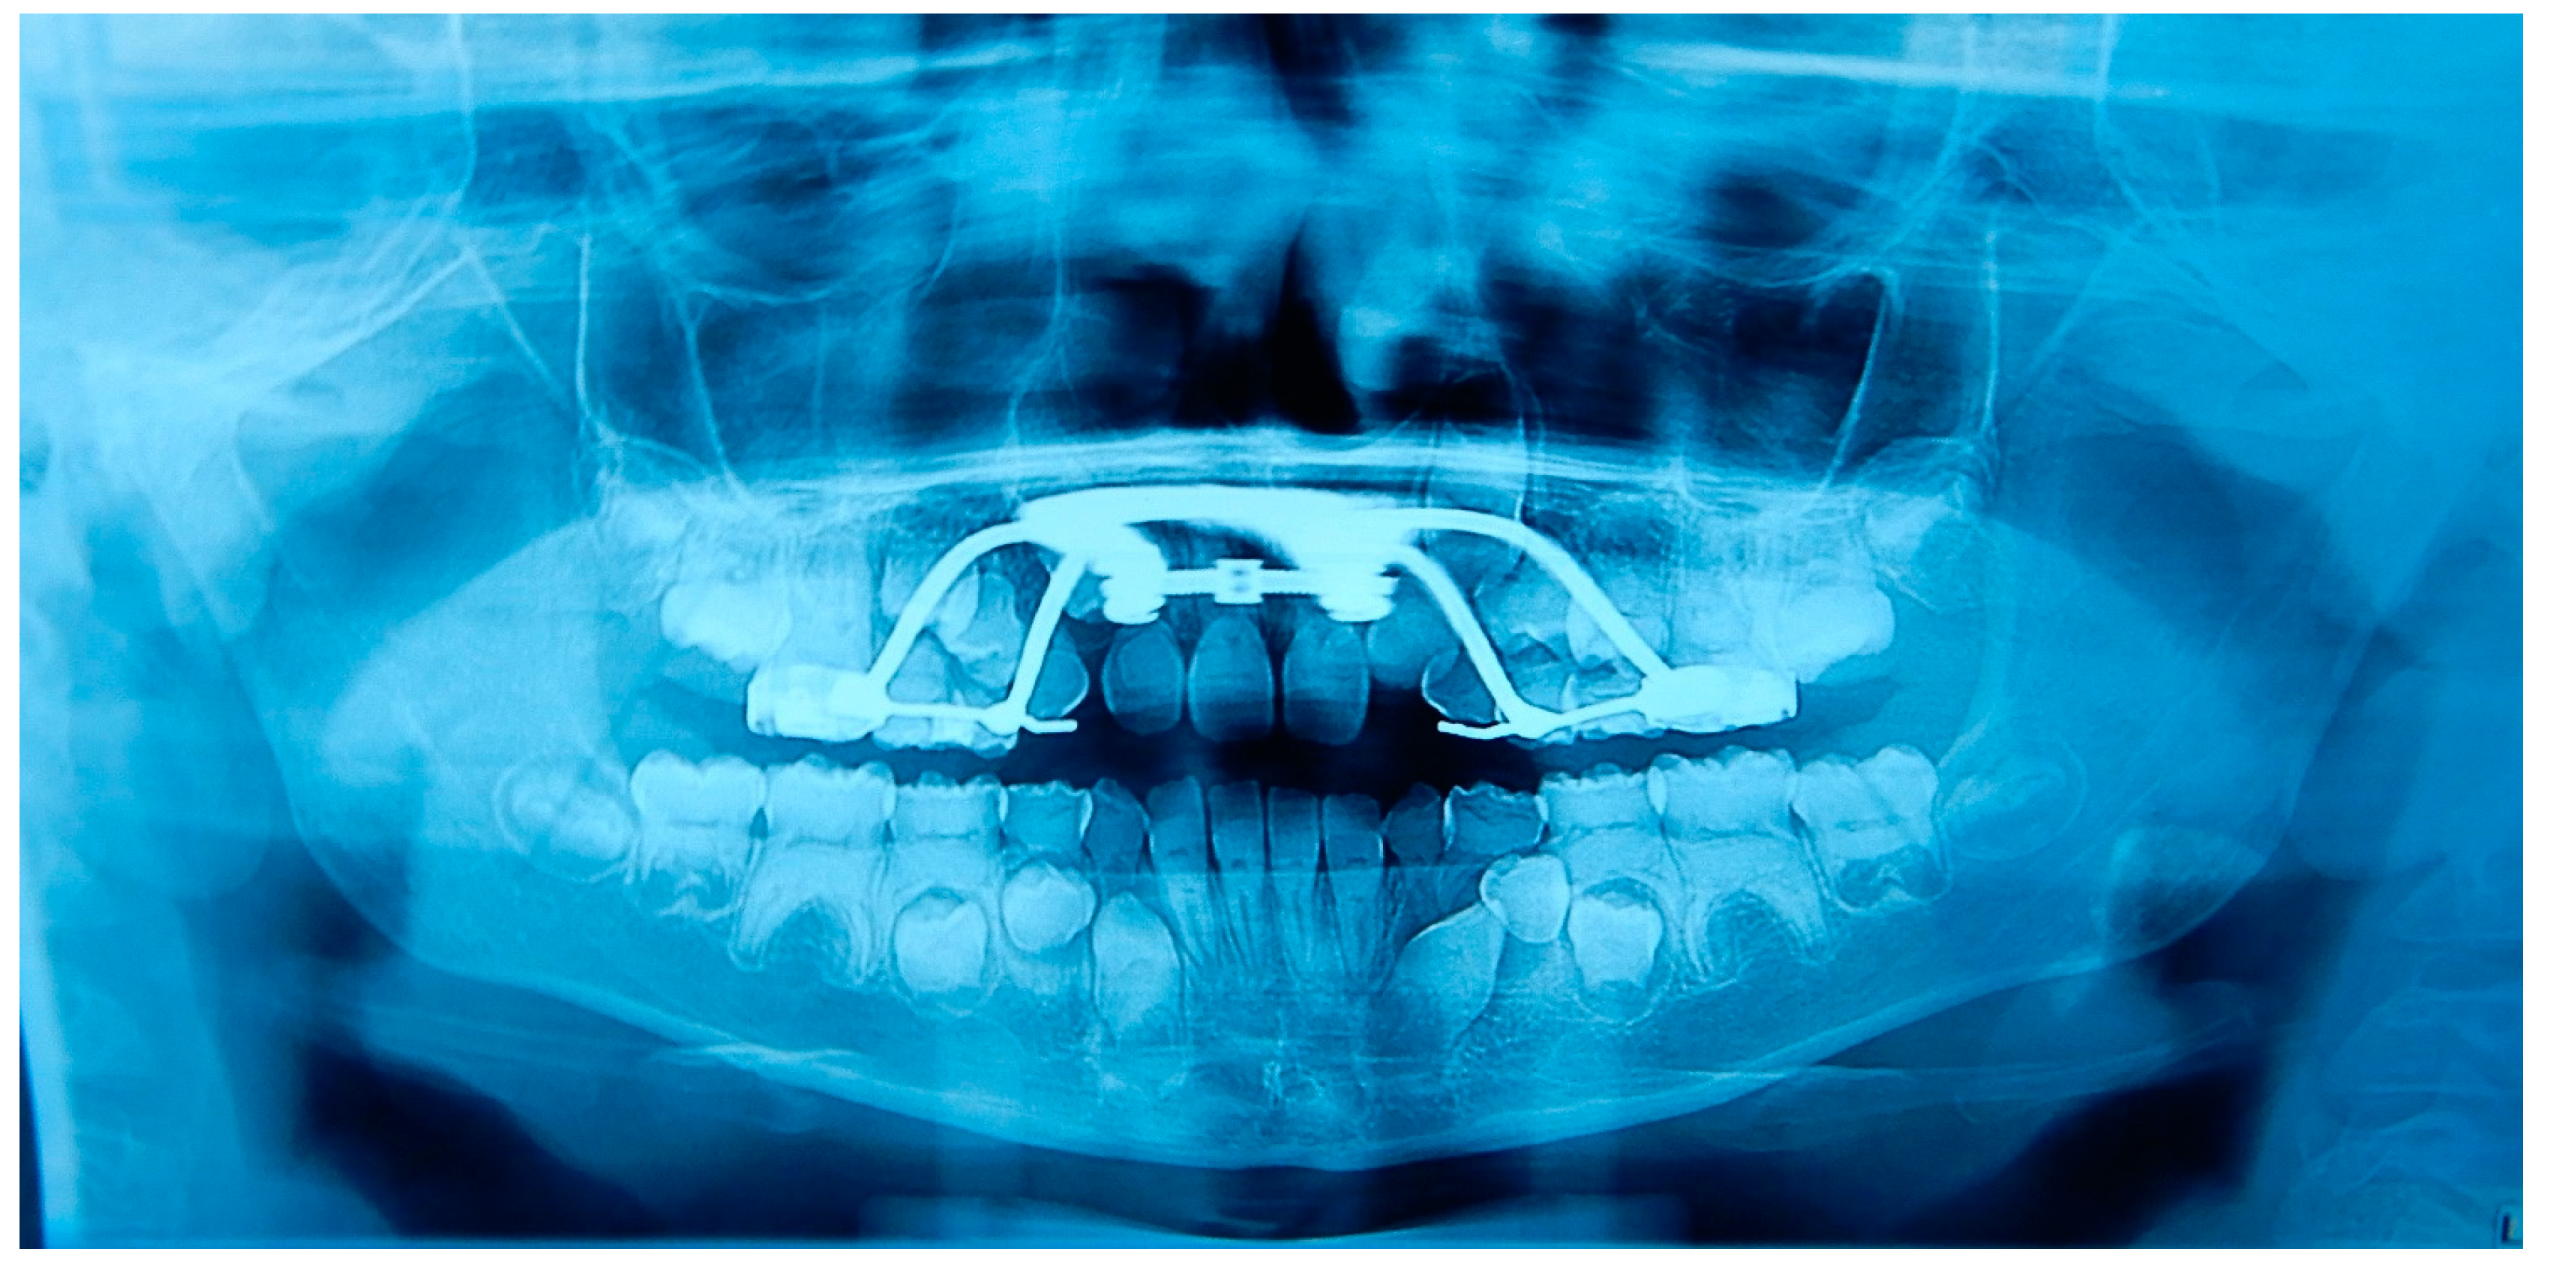

2.6. Dental Management of the Affected Children and Father

3. Discussion